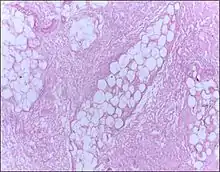

| Micrograph of breast tissue showing fat necrosis. H&E stain | |

Fat necrosis is a form of necrosis that is caused by the action of lipases on adipocytes.[1][2]

In fat necrosis, the enzyme lipase releases fatty acids from triglycerides. The fatty acids then complex with calcium to form soaps. These soaps appear as white chalky deposits.[3]

Fat necrosis is the pattern of damage associated with the destruction of adipose tissue by trauma, hypoxia, or lipase digestion (e.g. pancreatitis). In the classic case of fat necrosis in severe acute pancreatitis, the necrosis arises because adipocytes in the peritoneum are broken and digested by inappropriately activated pancreatic enzymes. Stored triglycerides in the adipocytes are released and split by pancreatic lipases into fatty acids and glycerol molecules. The resultant fatty acids react with extracellular calcium to make calcium soaps (i.e. fatty acid salts) that give fat necrosis its characteristic chalky-white appearance. Fat necrosis is an example of dystrophic calcification because the calcification occurs at normal serum calcium levels.[11]